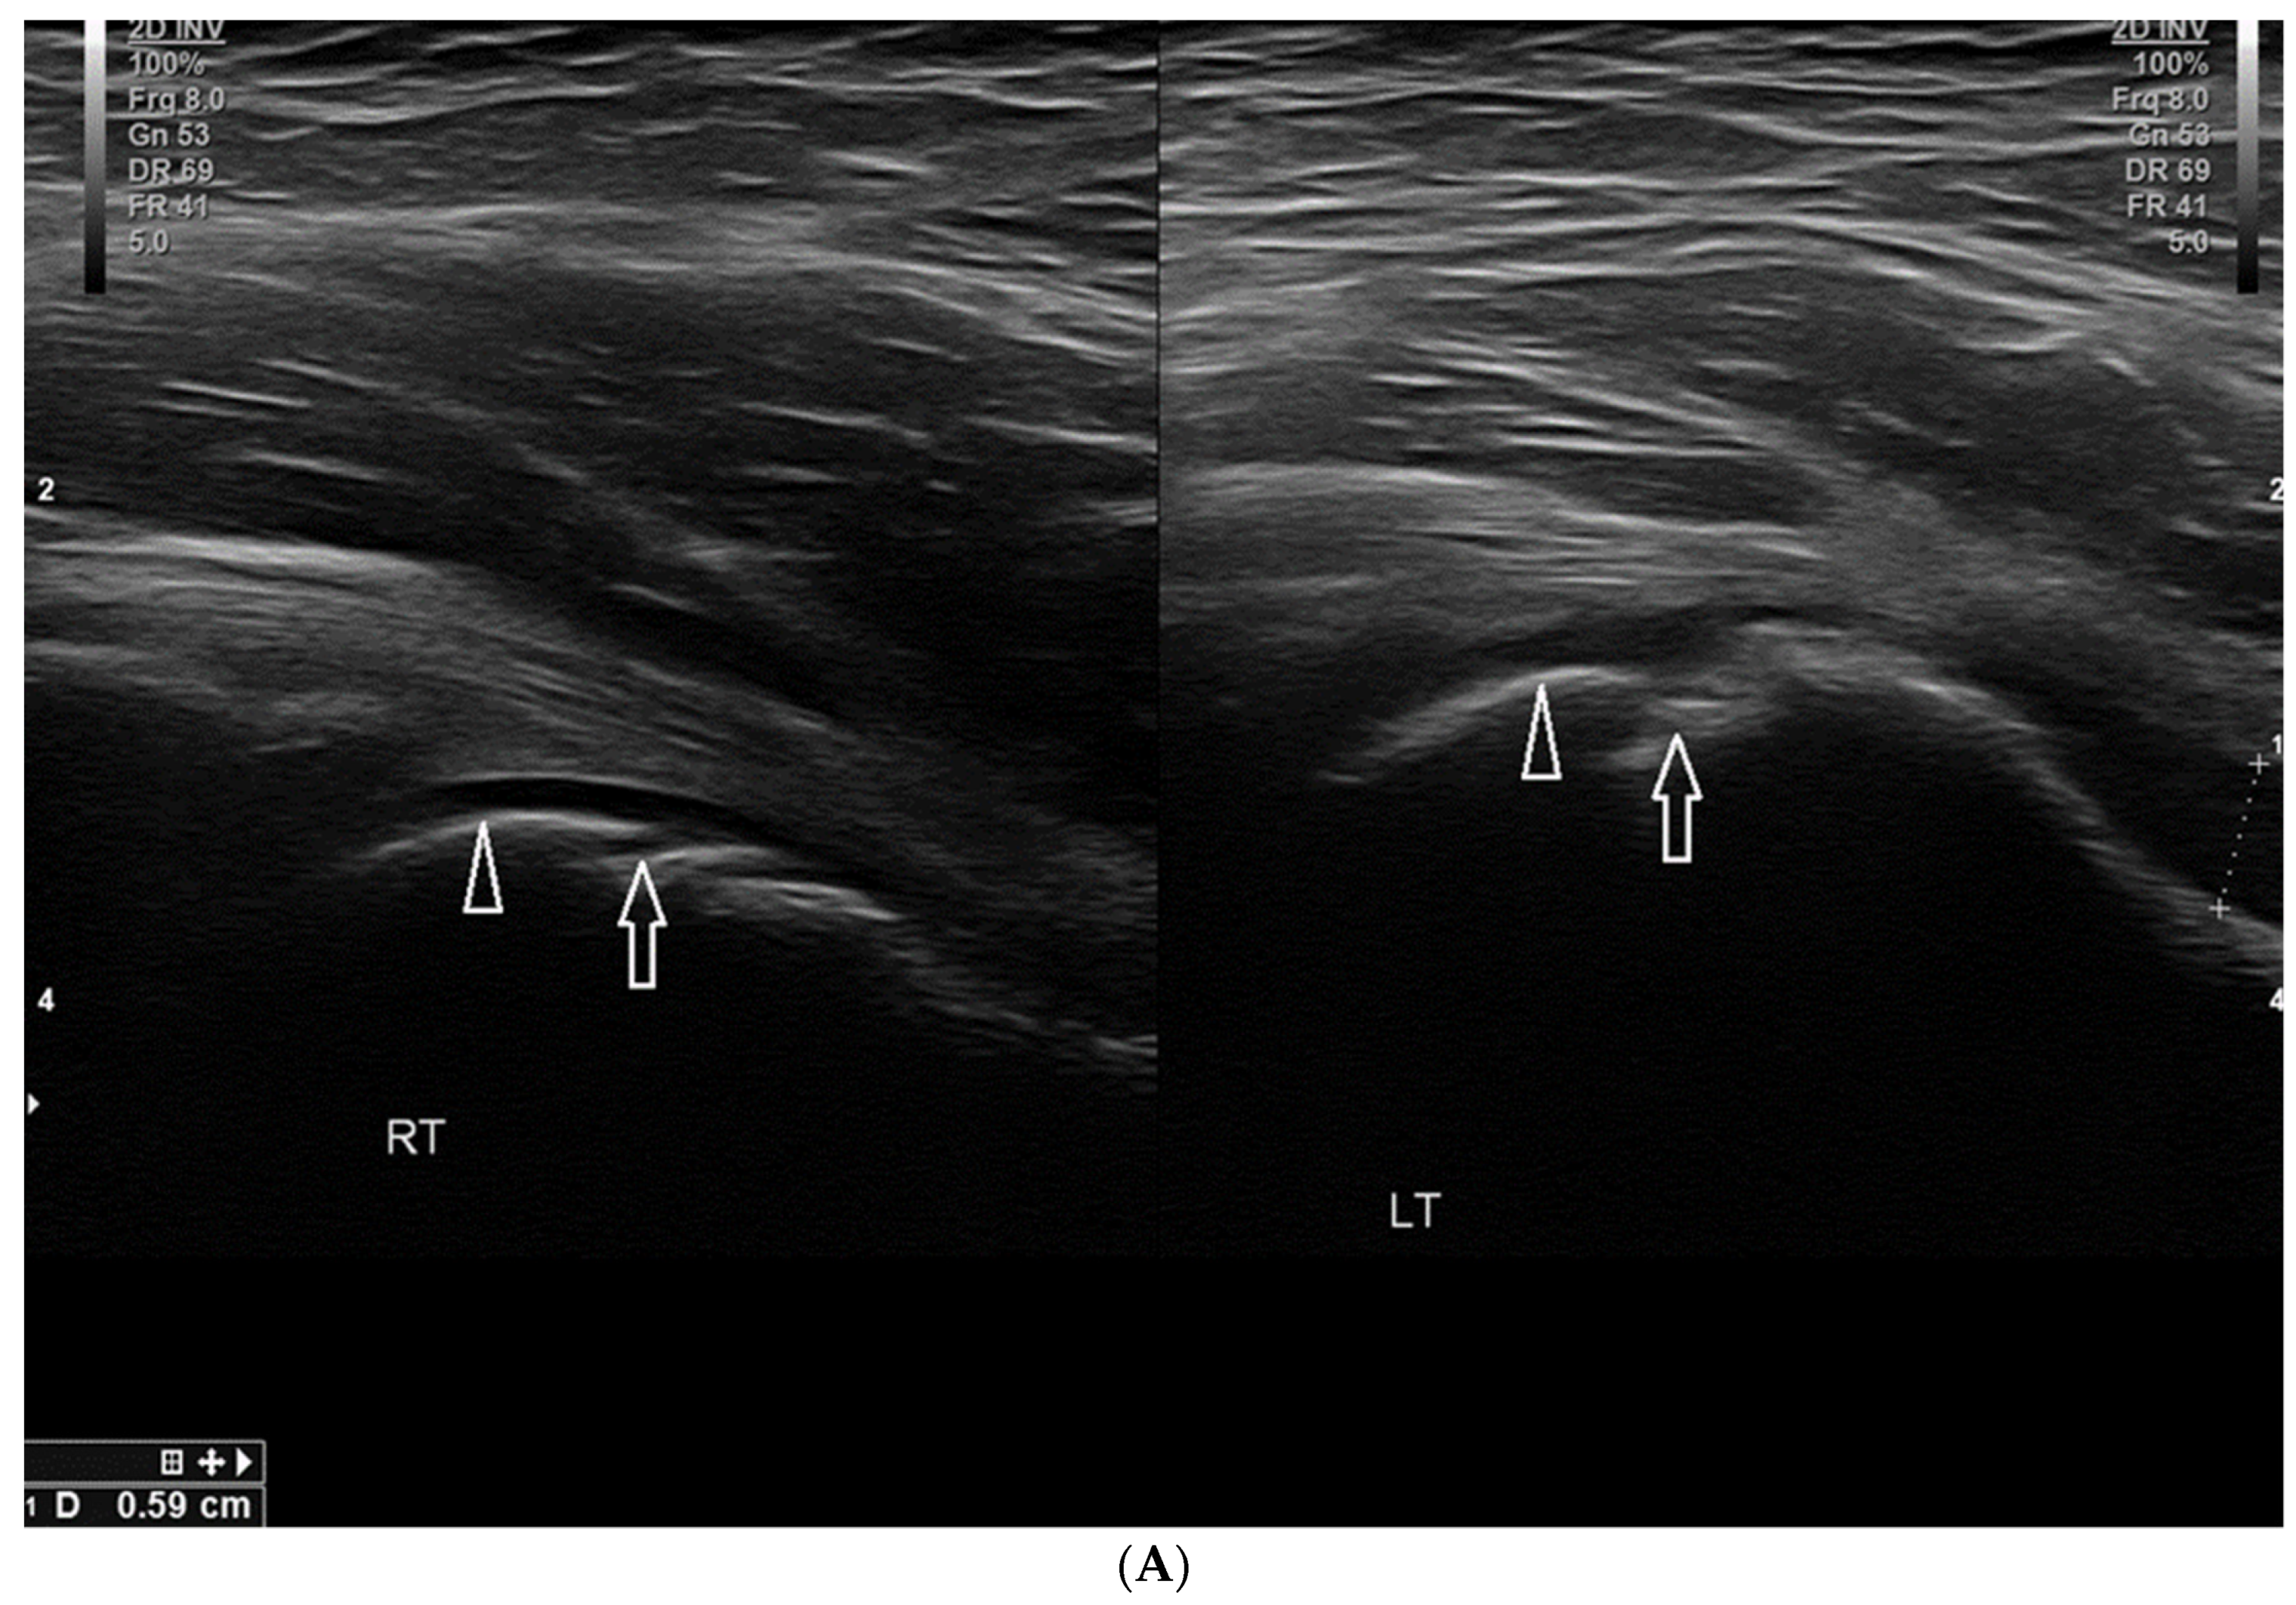

3.2.2. Osgood–Schlatter Disease